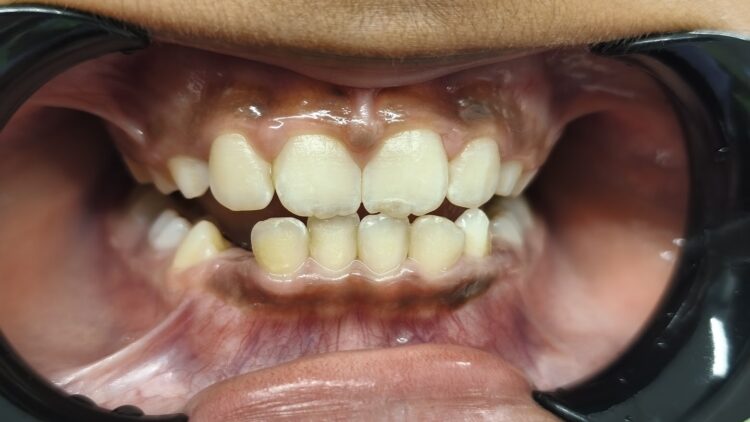

Before

The young patient presented with noticeable plaque and tartar buildup, particularly along the gum line. The gums were irritated, showing redness and early signs of inflammation, which caused sensitivity and unpleasant breath.